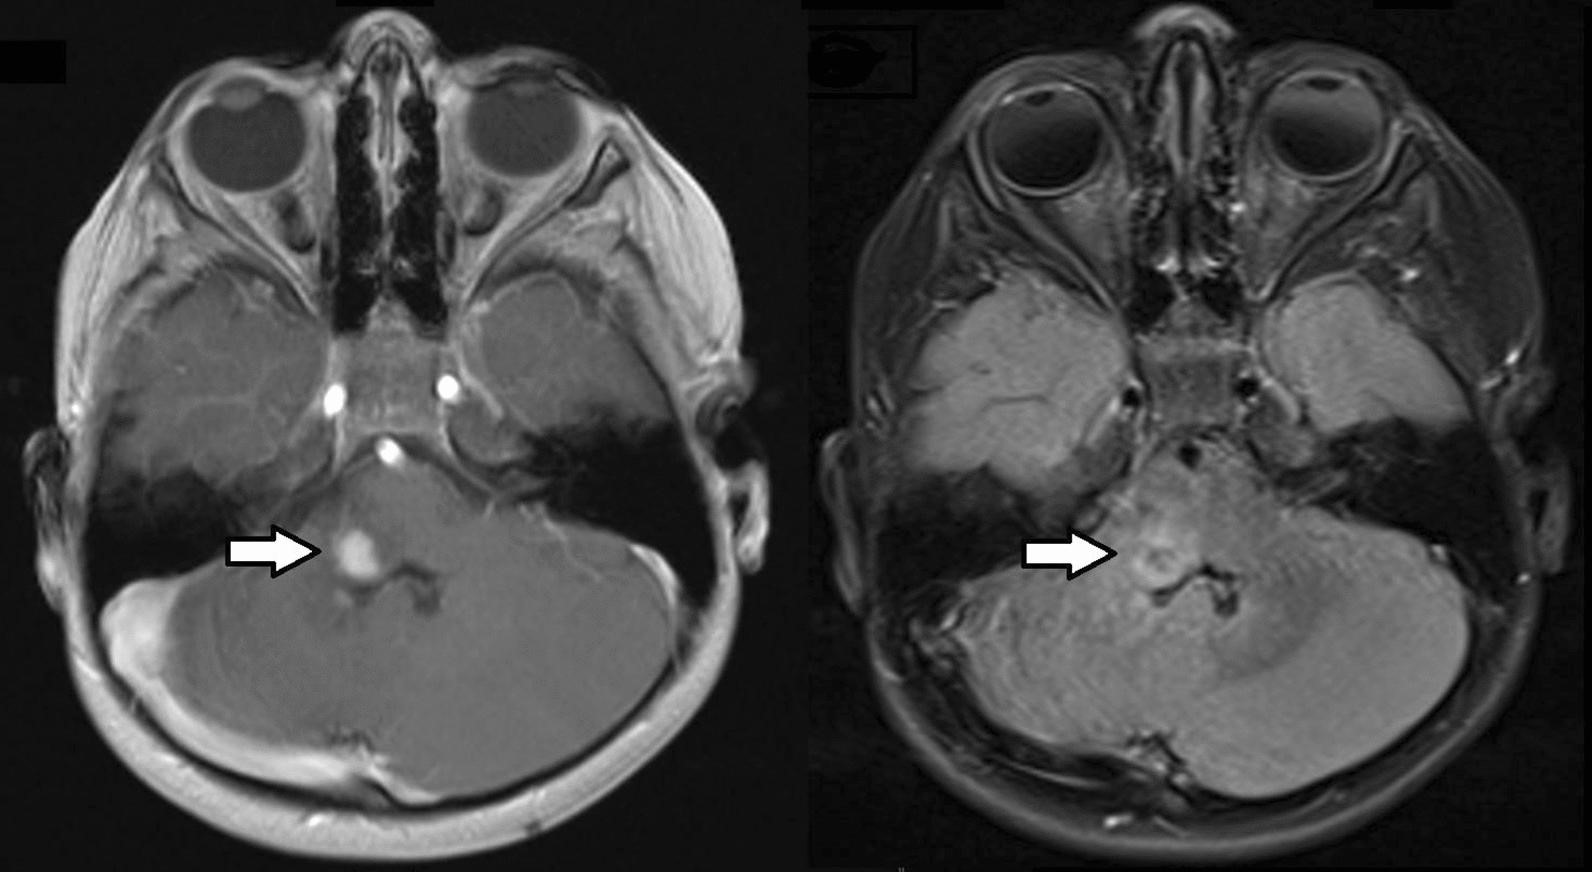

一名 4 岁女性接受了右侧髓质神经鞘瘤的次全切除术。在进行性头部倾斜的磁共振成像 (MRI) 上发现了肿瘤(图 1)。既往病史因发育迟缓和面部不对称(半面小儿)而显著。在 18 个月大时进行的先前 MRI 显示小脑发育不全,但没有肿瘤。在佳学基因进行致病基因鉴定基因解码前,采用的包括生殖系靶向基因检测包基因检测和全外显子组测序在内的综合临床基因检查结果为阴性。诊断后 8 个月的最近一次脑部 MRI 随访显示稳定的残留病灶。

图1:T1 加权增强后(左图)和 T2/FLAIR 加权(右图)磁共振图像显示部分增强的实质内右侧髓质肿瘤(箭头)。肿瘤累及下脑桥右侧、脑桥臂和小脑腹侧